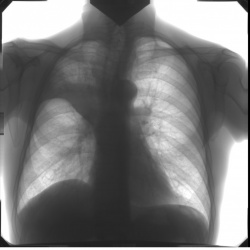

Девочка. Давно болеет. После рентгена КаТали уже. Пневмония движется. Коллеги, подскажете направление?.. С пятном справа - первый, контроль - без него.